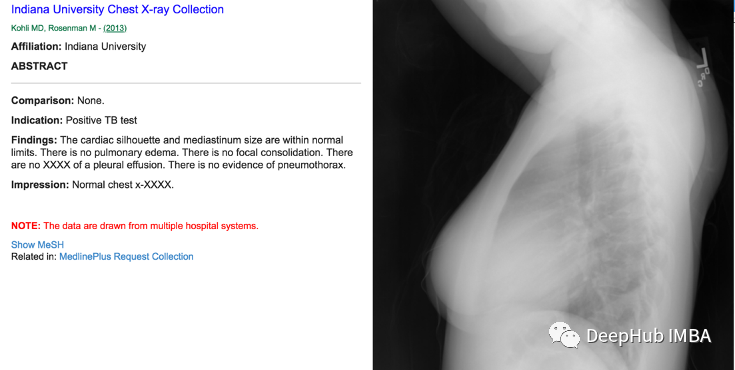

放射科医生将查看这些成像测试的结果,找到评估和支持诊断的相关图像。患者完成影像学检查后,放射科医生将向临床医生提供他们的解释报告。典型的放射学报告包括以下部分:检查名称或类型、检查日期、MeSH(医学主题词库)、解释放射科医师详细信息、临床病史等,

数据大小:20.7 MB,报告总数:3955,我们可以使用xml.etree.ElementTree解析XML报告,Xml包含以下重要数据,需要从Xml中提取。

1、适应症:该数据描述了研究原因和/或适用的临床信息或诊断的简单、简洁的陈述。 对适应症的清晰理解也可以阐明研究应解决的适当临床问题。例如:结核病检测阳性、胸痛等,

2、对比:该数据描述了是否将这种新的成像检查与任何可用的先前检查进行比较。 比较通常涉及相同身体部位和检查类型的检查。

3、发现:该数据列出了放射科医生在检查中身体各个部位的观察结果。 这记录了该区域是否被认为是正常、异常或潜在异常。例如心脏大小正常。 纵隔无异常。 肺清净等,

4、 结果:该数据包含调查结果的摘要,并报告他们看到的最重要的调查结果以及这些调查结果的可能原因。 本节提供了最重要的决策信息。例如无急性病、清肺等,

整合上面的2个信息简单的可视化如下: